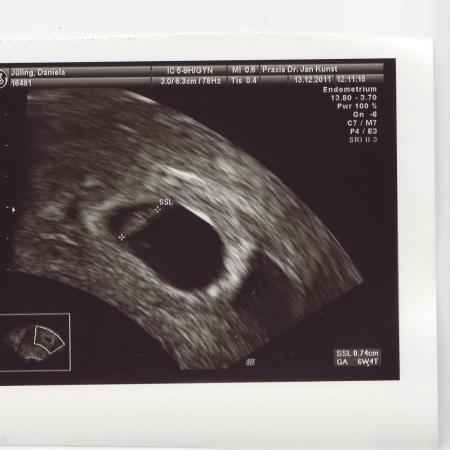

mein ich das nur oder sieht mein US Bild anders aus als eure? Bei mir sieht man nur die Fruchtblase und den kleinen Krümmel der schon 4mm groß sein soll... Muss ich mir sorgen machen? Eure hier im Forum sehen irgendwie anders aus... :-( klar sind nicht alle gleich, aber wegen meiner Blutungen mach ich mir da irgendwie gedanken... Glg Tina

Bild zu Mein US Bild sieht irgenwie anders aus als euers... - Forum für August - Mamis

Also ich finde es sieht normal aus. Hab jetzt zwar keins bekommen aber von meiner 1 ssw. das sieht ähnlich aus.

Das ist ein ganz normales US-Bildchen für die 6. SSW. Es gibt viele, die können in der Zeit noch nicht so ein schönes Bild vorweisen. Es gibt natürlich auch welche, bei denen man mehr sieht... keine Angst, jedes Krümelchen entwickelt sich unterschiedlich. Ich finde, es ist ein gutes Bild!